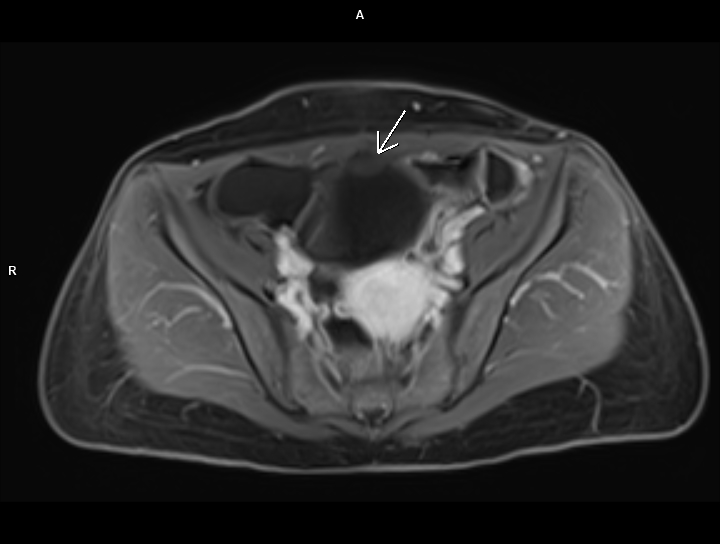

Figurile 3 si 4: axial T1 postcontrast cu saturaţia grăsimii

Discuţie caz nr 83: chistul de uracă apare datorită faptului ca uraca nu s-a inchis complet în timpul dezvoltării fetale si este un buzunar umplut cu lichid; uraca este o structură embriologică normală care leagă vezica fetală de cordonul ombilical. Majoritatea chistelor uracale sunt asimptomatice, însă uneori se pot infecta şi pot provoca complicații: simptome ale tractului urinar, hematurie sau o masă palpabilă.

Chistele de uraca se datorează faptului că uraca nu s-a închis în primul trimestru de sarcina; pot fi descoperiri întâmplătoare la examinările imagistice sau se pot complica.